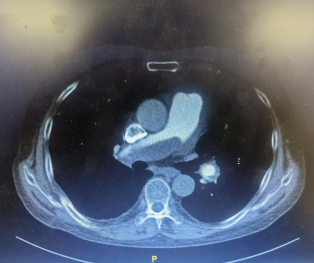

入院后,徐鸥主任第一时间与心外三病区张恒主任联系,对熊大爷的手术指征进行全面评估。于3月3日转入心外三病区后,先后进行了冠状动脉造影、先心病导管+造影,肺动脉增强CTA,心脏超声等一系列相关检查,提示主肺动脉、左右肺动脉干及双肺下叶肺动脉干管腔内多发充盈缺损影,左肺上叶、右肺中叶、下叶多发肺动脉分支官腔纤细、闭塞。经过肺血管与综合内科病区徐鸥主任和心外科病区王小啟主任经过多学科综合讨论下指定了详尽的手术方案,十余日的精心术前准备,于3月17日顺利进行了肺动脉内膜剥脱术,肺动脉血栓清除术:术中采用全身低温体外循环,期间行深低温停循环2min,使用剥离子仔细分离肺动脉内膜及机化血栓直至右侧肺叶动脉分叉处,并将血栓及内膜整块剥出。手术顺利,熊大爷于术后第4日状态平稳从SICU转回病房,氧分压(P02)从本次入院51.5mmHg升至出院时67.7mmHg,血氧浓度(SO2)吸氧后从85.4%升至92.6%,超声示肺动脉高压(重度)降至轻度肺动脉高压,于4月3日顺利出院。